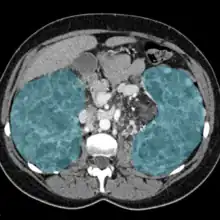

| Showing both enlarged kidneys in blue. | |

Nephromegaly is the process whereby a kidney or both kidneys become enlarged.[1] Both autosomal dominant and autosomal recessive polycystic kidney disease can cause nephromegaly.